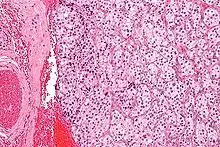

On microscopic inspection, the tumor cells are readily recognized. Individual tumor cells are polygonal to oval and are arranged in distinctive cell balls, called Zellballen.[8] These cell balls are separated by fibrovascular stroma and surrounded by sustentacular cells.

Micrograph of a carotid body tumor